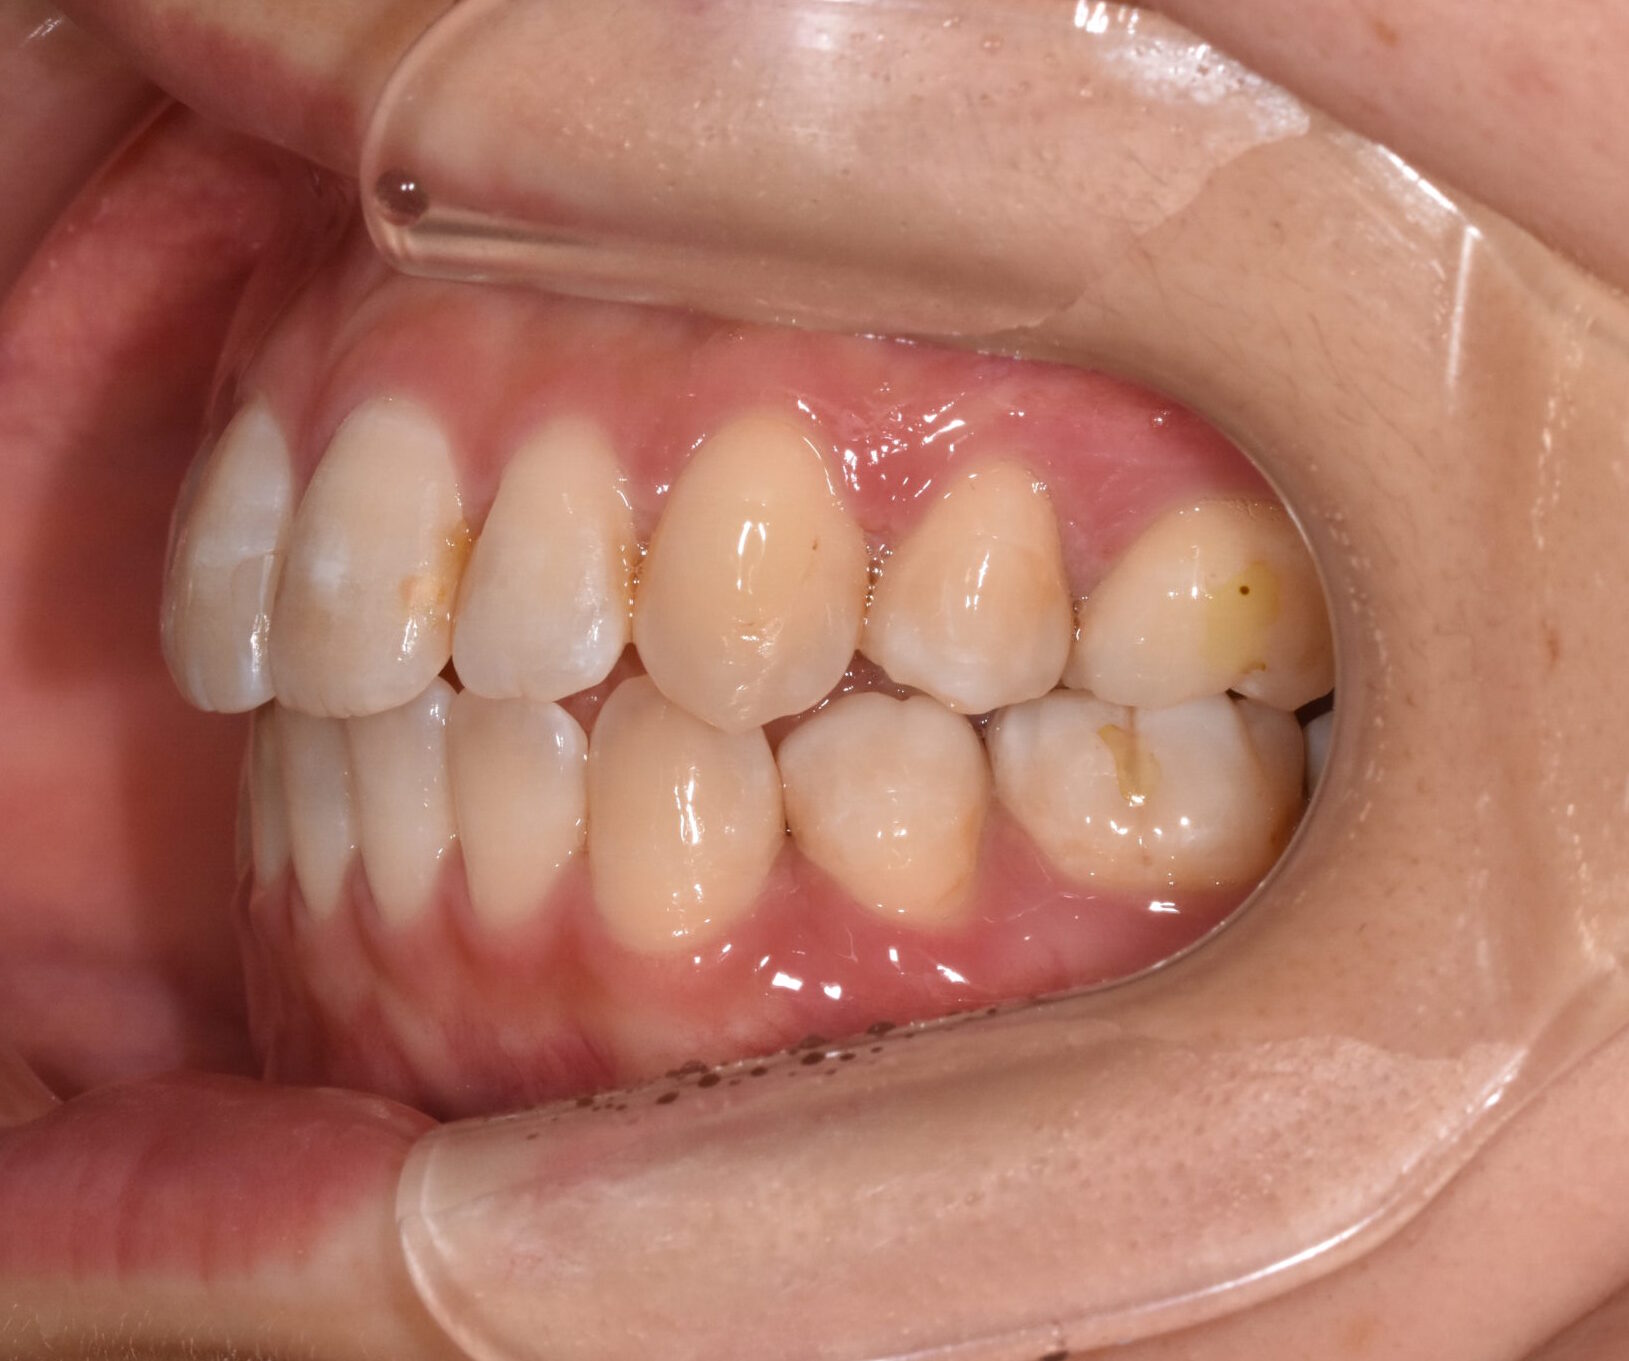

開咬 17歳 女性

治療前

骨格:開咬傾向(前歯が噛みにくいタイプ)

歯並び:前歯が噛み合わない(開咬)+前歯の突出傾向